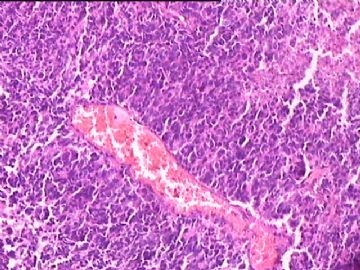

女,34y,头痛一月,右额叶占位:5*5*4cm。囊性区域,4cm。大体:3.5x3x1cm灰白间暗褐色组织一堆,质嫩。临床诊断1:胶质瘤,2:血管母细胞瘤。

• 额叶占位,胶母典型不?图2

图2

胶母

同意胶质母细胞瘤。细胞异型、坏死、核分裂、血管内皮肿胀增生均可见到。

This is certainly a WHO grade IV malignant neoplasm. While most likely a glioblastoma, I would carefully rule out PNET by staining for GFAP and neuronal markers such as synaptophysin, NeuN and NSE. Rarely, PNET may shows marked pleomorphism and indistinguishable from glioblastoma on HE stain.

同意马老师的意见,该肿瘤从形态及年龄来看考虑PNET或GBM,须标记Syn、NSE、S-100、NeuN和GFAP来鉴别。

结合图片细胞形态特点考虑胶质母细胞瘤,组化标记排除其他